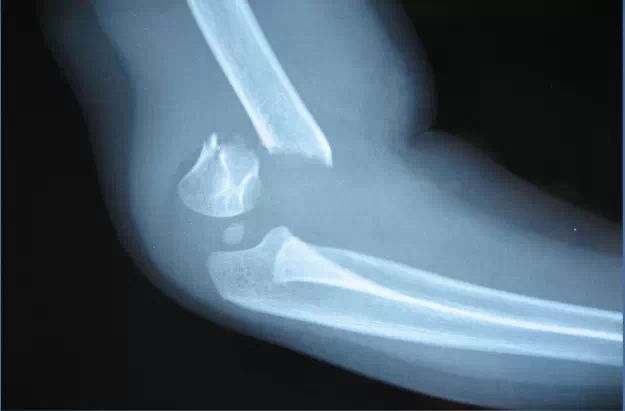

病史,體征;正規正側位X就能確診骨折,及分型;主要鑒別於肘關節脫位(見下文)。

肘關節脫位

是四肢關節脫位中第2位常見類型,肘關節處於半伸直位時跌倒,手掌著地,由暴力沿前臂傳至肘關節導致;當前臂內、外翻時遭受暴力也可造成肘關節脫位。

肱骨髁上骨折與肘關節脫位鑒別要點

1、肱骨髁上骨折(申直型):肘關節可部分活動、肘後三角無變化、上臂短縮、前臂正常。

2、肘關節脫位:肘關節彈性固定、肘後三角有變化、上臂正常、前臂短。

所謂的肘後三角即當肘部彎曲時可以從內到外摸到的3個突出的骨頭,一般情況下3者間位置是固定的。簡單而言,肘關節脫位時:肘關節後方可有凹陷區域,其餘表現與上述肘部骨折類似。治療以手法複位為主,若合並韌帶損傷則需手術治療。